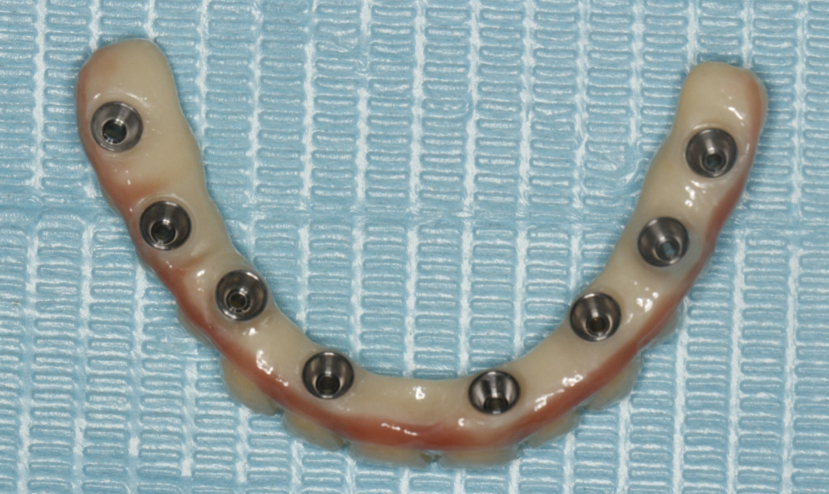

该患者就是因牙周病导致牙齿松动脱落,我们通过在半口牙槽骨上植入8颗种植体,然后在种植体上安装连桥牙冠,从而恢复半口牙齿的咀嚼功能和美观。相对于传统的种植修复方式缺一颗种一颗。4-8颗种植体的种植手术创伤相对较小,大大的减少了患者的疼痛感。